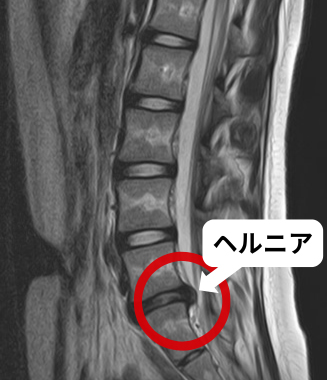

この椎間板の周辺部分である線維輪の亀裂から、椎間板の中心部分である髄核が脱出し、神経を圧迫して、腰痛やお尻の痛み、足先に放散する痛み、シビレ、足に力が入らなくなった状態(いわゆる根性坐骨神経痛)を腰椎椎間板ヘルニアと言います。

当院には腰椎椎間板ヘルニアと診断されて手術をしたが症状が良くならなかったり、元の症状は良くなったが手術前とは違う場所に症状が出てきた、といった方が多数来院されます。これは、現在の整形外科に「関節の機能障害が痛みやシビレ等の症状を起こす」という概念がないためです。関節の機能障害はMRI等の静止画像ではわかりません。痛みの原因がMRIに写るヘルニアであれば手術をすれば治癒します。しかし原因が関節の機能障害の場合は手術をしても痛みが治る事はありません。